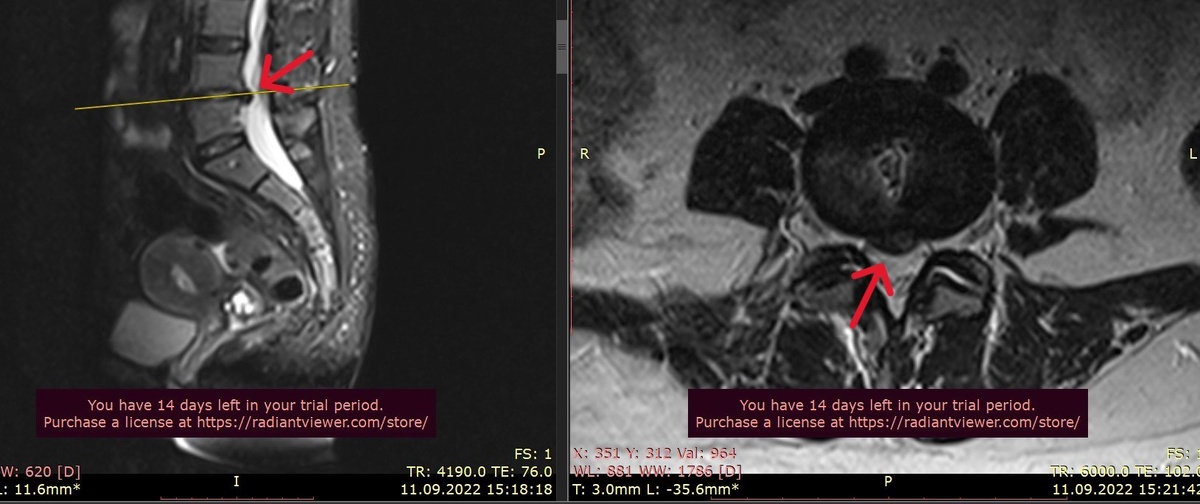

На МРТ обнаружили достаточно большую медианную грыжу на уровне L4–L5.

А на контрольном МРТ грыжа уменьшилась.